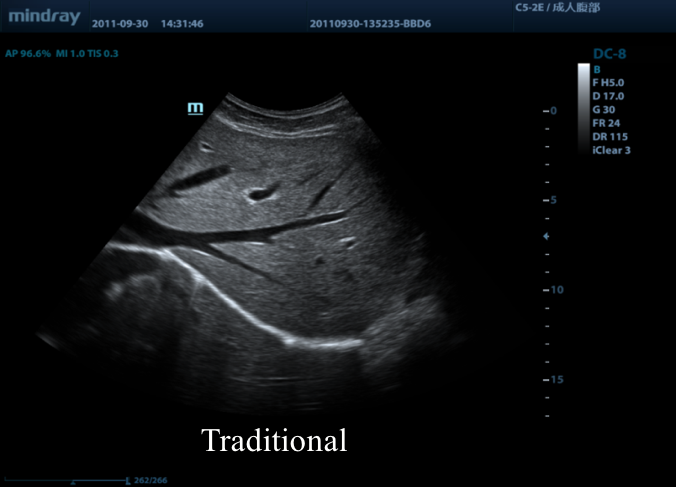

Предлагаем вам ознакомиться с примером применения данной технологии. Изображения выполнены на приборе Mindray DC-8, на верхнем изображении режим iBeam (компаундинг) отключен, а на нижнем включен на первую ступень регулировки (3 луча).

14.png

15.png